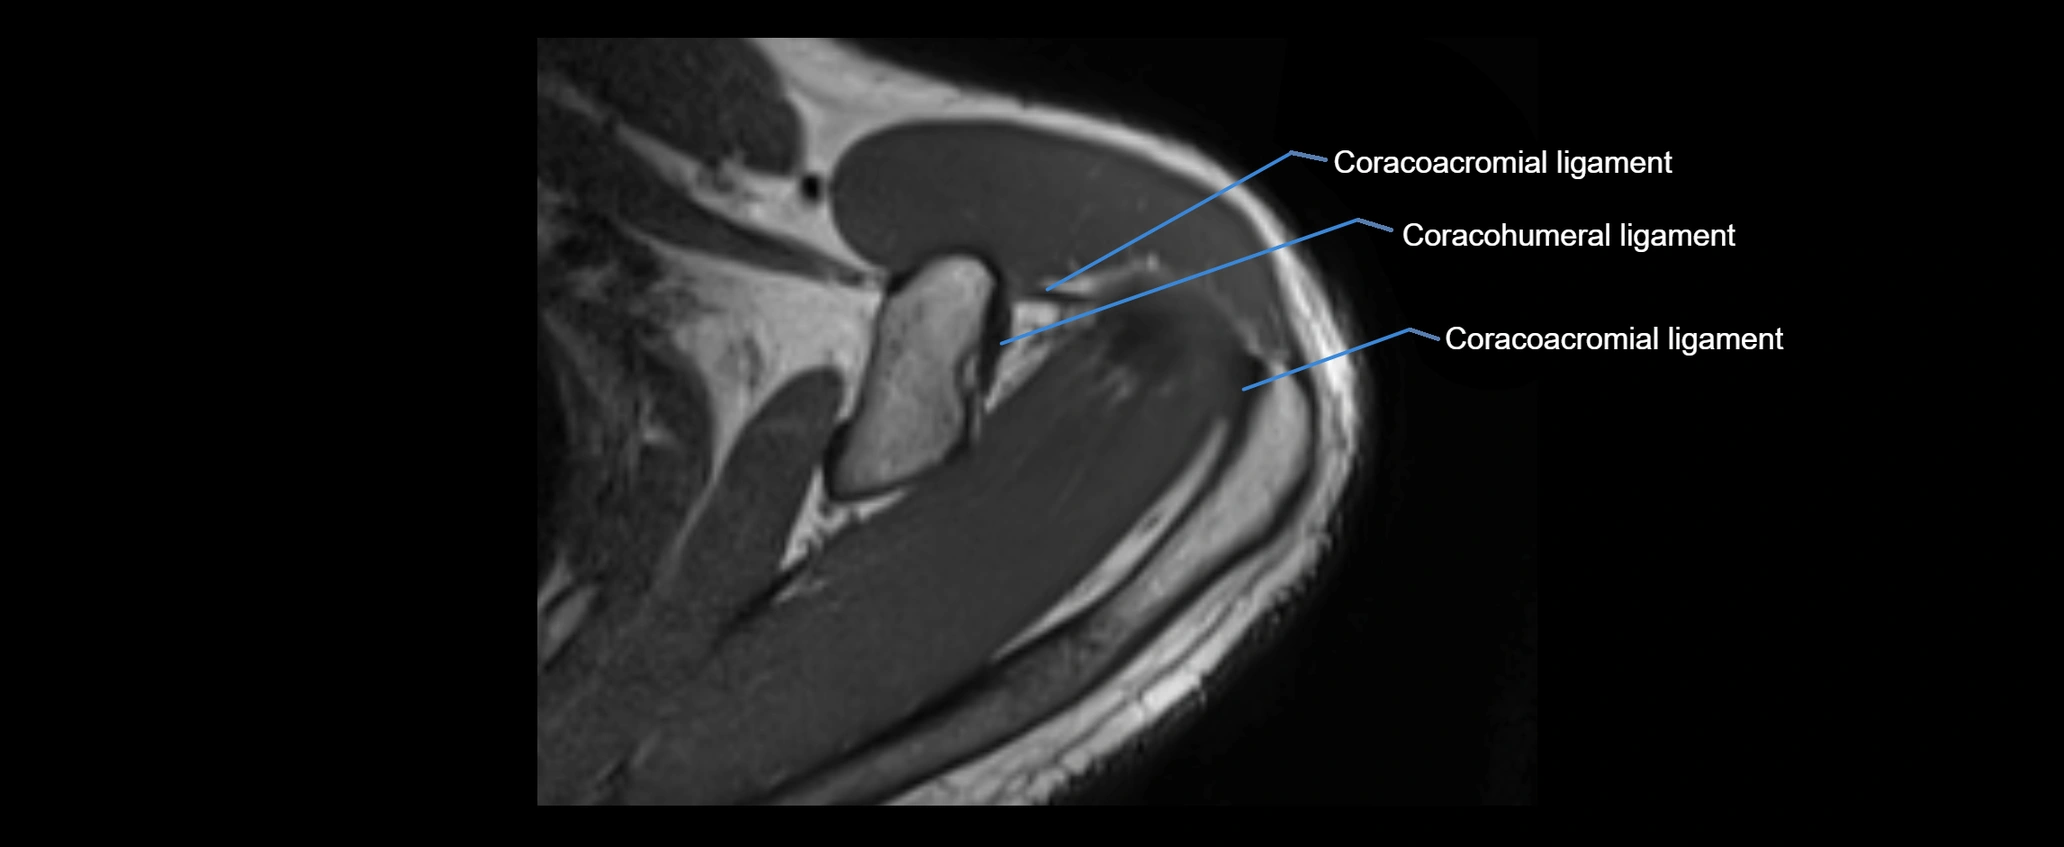

MRI images

image